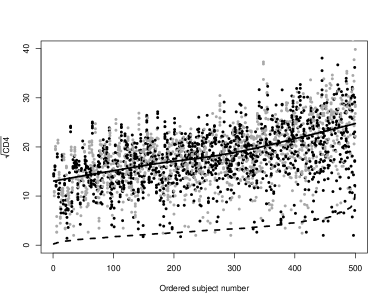

One of the common and major assumptions in longitudinal models is that the within-individual variances are homogeneous, although this is not always satisfied. For example, considering our dataset (section 4.1), the plot of the individual values against the standard deviation (Figure 1) suggests considerable within-subject variance heterogeneity. Large values of the mean are associated with high variability. In equation (3) the residual variance, , is assumed to be an individual property allowing for heterogeneity in the variance trends among the individuals. Modelling it and identify covariates related to this discrepancies seems wise. Particularly, in many HIV/AIDS studies, where investigators are interested in understanding the trends of the variability, having an individual estimate of the subject-residual variance can be a plus in the assessment of whether individuals with different biomarker’s stability have different prognosis.

Our main concern in this work is to use joint modelling for making appropriate inferences about the influence of the longitudinal data characteristics on the survival time. Table 1 shows the form of the 33 joint models fitted to the data and the respective WAIC values for comparison. A square root transformation of the CD4, , was used in the analysis in order to deal with the high degree of skewness towards the higher counts. Its adjusted longitudinal mean response, , has always the following representation